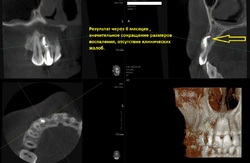

Через 6 месяцев отмечается практически полное восстановление костной ткани вокруг корня зуба.